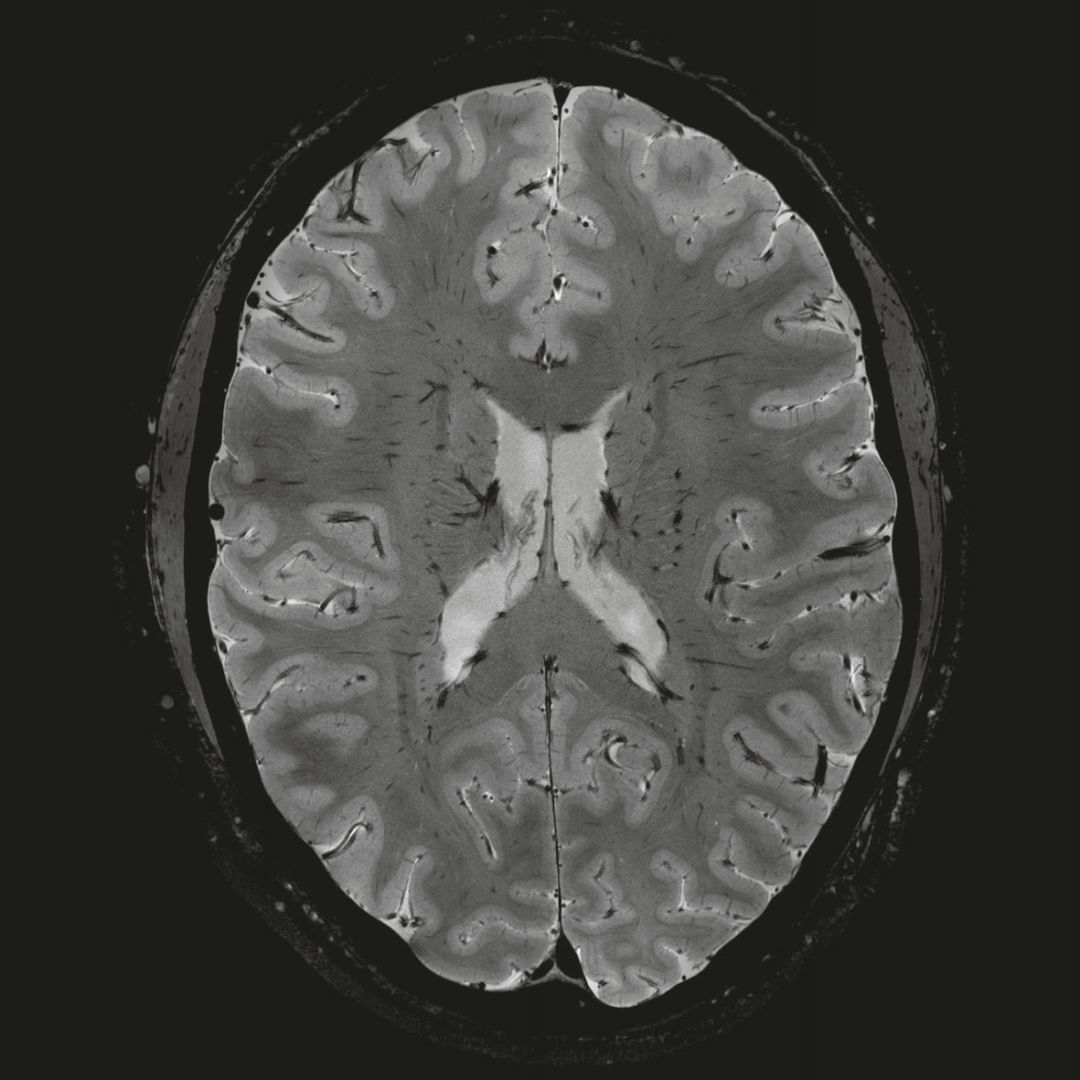

1毫米的各向同性分辨率DTI:神經(jīng)纖維束的交叉細(xì)節(jié)顯示

0.8毫米的各向同性分辨率:精確劃分灰質(zhì)和白質(zhì)

0.8毫米的各向同性分辨率:超精細(xì)的解剖細(xì)節(jié),例:小腦的精細(xì)結(jié)構(gòu)

超精細(xì)的解剖細(xì)節(jié):T2對(duì)比

0.17 x 0.17 x 0.8毫米分辨率超高。